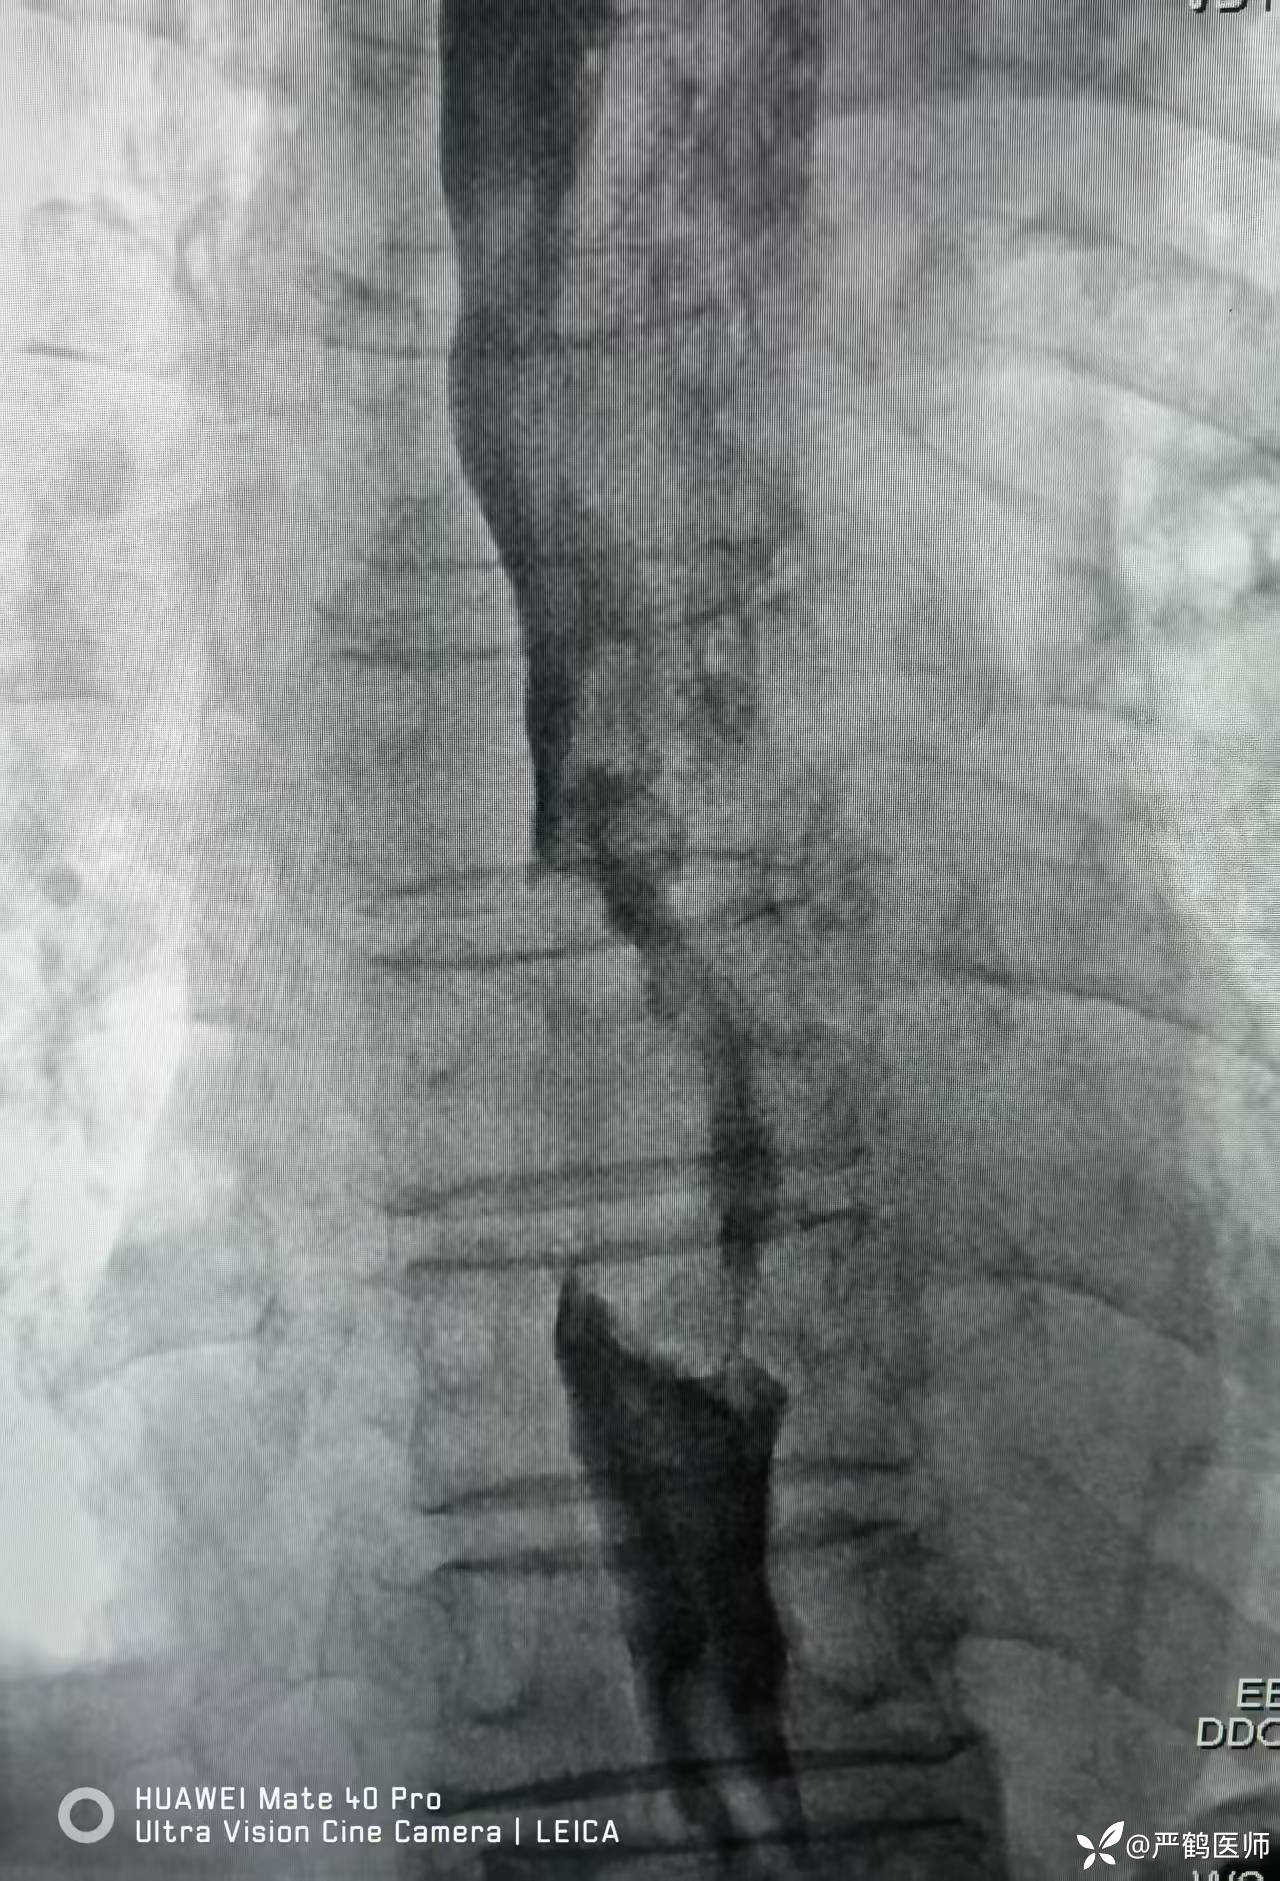

食管癌覆膜支架置入术

老年男性,食管距门齿30cm处肿瘤至进食梗阻,无法手术,家属不愿进一步行放化疗治疗,置入全覆膜食管支架解除梗阻,缓解进食困难症状